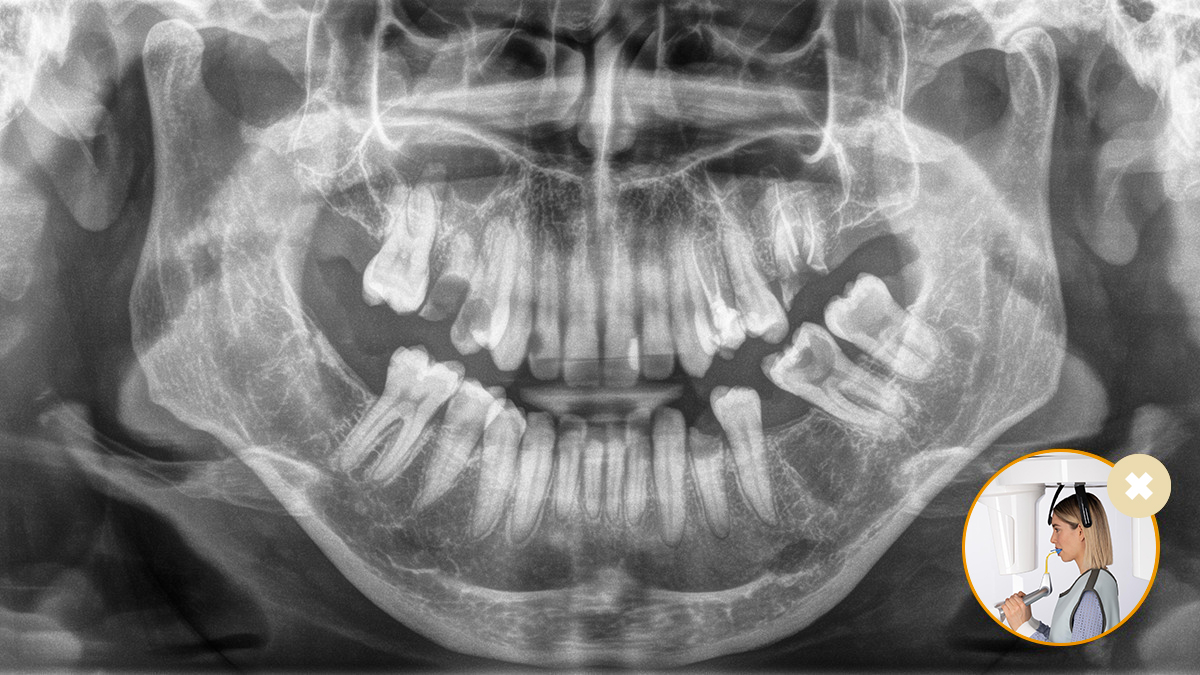

El posicionamiento correcto del paciente permite obtener imágenes de alta calidad que respaldan un diagnóstico preciso y facilitan y mejoran la experiencia del paciente.

Este es nuestro concepto de 10 puntos para facilitar el posicionamiento del paciente y la obtención de imágenes radiológicas. Se trata principalmente de dos cosas: alta calidad de imagen y comodidad para el paciente y el asistente.